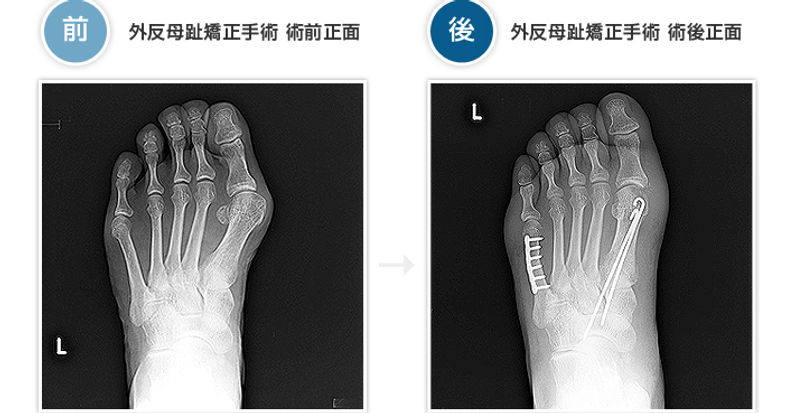

• 足の外科手術 | 医療法人隼整会

• 整形外科サージカルテクニック 2024年4号〈特集〉変形性足関節症